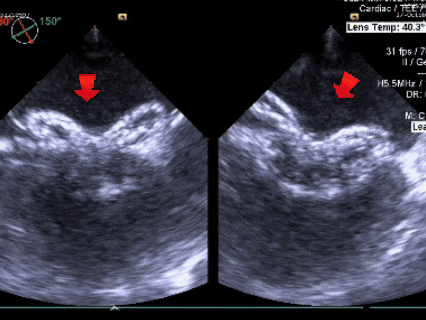

成型锁定

鞘管抵住封堵器后,前顶钢缆,

固定钢缆和鞘管,牵拉成型线锁定

锁定后牵拉试验

锁定后,封堵器形态良好,进行牵拉试验,

超声下可见封堵器整体移动,右盘面未被拉开

锁定后评估

彩色多普勒血流成像显示无残余分流存在